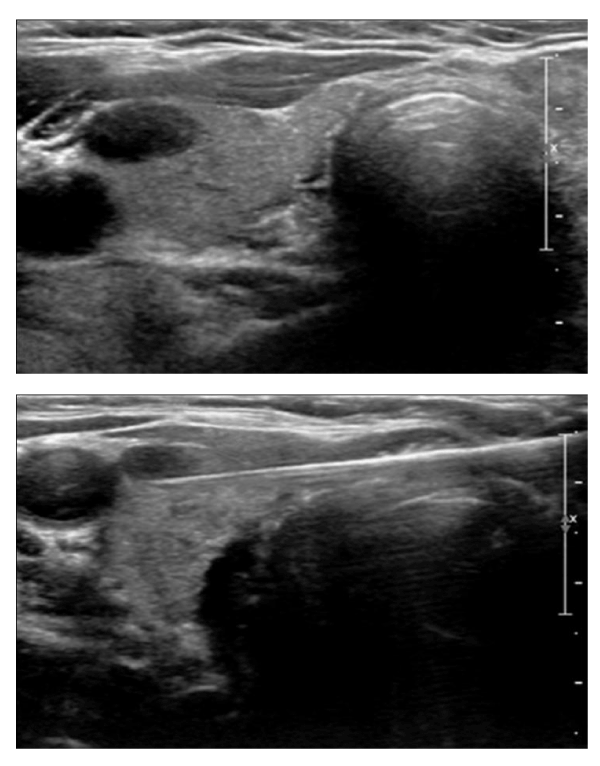

| Figure 2: A 21-year-old Caucasian woman with non-Hodgkin lymphoma. (a) US which reveals an intraparenchymal ill-defined hypoechoic nodule corresponding to a palpable mass on physical exam in the upper right lobe (20 mm). PROTOCOL: iU22 with a probe center frequency of 9-12 MHz (Philips). (b) By fine needle aspiration cytology under ultrasound guidance at the sn lobe cytology: Thyroid hyperplasia (TIR2) with a carpet of macrophages. |